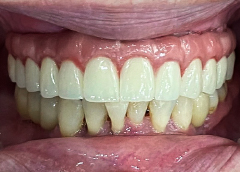

• Răng sứ sử dụng:Răng toàn sứ Nacera 9Max Đức

• Phục hình răng toàn sứ Nacera 9Max Đức

“Sau khi làm răng cô ăn uống tốt hơn, thoải mái mà không kiêng cữ như trước, còn về thẩm mỹ thì gương mặt mình nó cũng đẹp lên, không còn hóp háp như trước kia. Nên mỗi khi ra ngoài cô cũng tự tin giao tiếp hơn” – cô Phương vui vẻ chia sẻ.